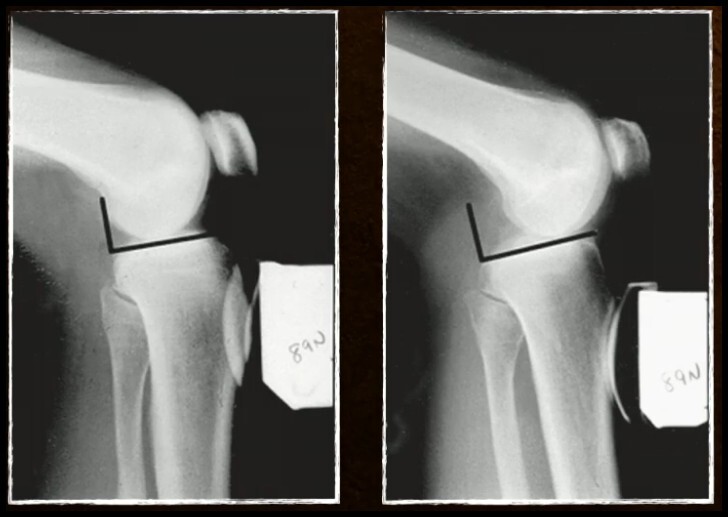

Imagem Radiográfica (2)

• Perfil com flexão 70º e Força 89N

• Lesão do LCP se Posteriorização > 8 mm